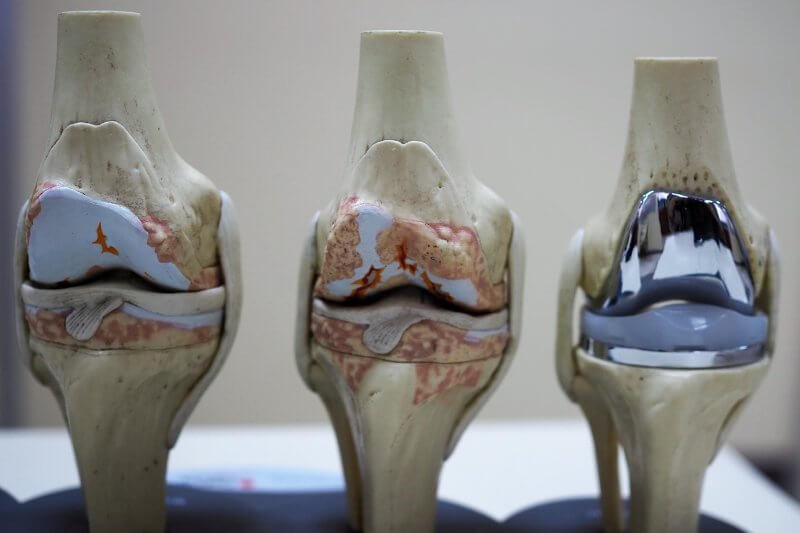

Knee arthroplasty is a surgical procedure involving the implantation of a knee prosthesis. This procedure is employed not only when the natural structures of the knee joint wear out due to aging but also when they are damaged as a result of trauma. Unfortunately, the knee joint’s anatomy predisposes it to such issues. The knee is the largest joint in the human body, connecting the thigh to the lower leg. It serves a critical function by bearing the entire body’s weight, stabilizing posture, and facilitating movement during daily activities and sports. The knee is a complex joint—a hinge-and-rotation joint—comprising numerous components such as bones, menisci, and ligaments, all encapsulated by a joint capsule. Degeneration of the knee joint weakens its structures and damages the articular cartilage.

Osteoarthritis of the knee is a condition with a multifactorial etiology. Various factors may predispose individuals to its development, such as lifestyle or occupational factors (e.g., prolonged standing with significant leg strain), past injuries to the lower limbs, or genetically determined limb axis abnormalities.

When the articular cartilage, which cushions the joint and provides smooth surfaces for the femur and tibia to move against each other, deteriorates or wears out completely, the bones begin to rub directly against each other, becoming rough and coarse. This triggers an inflammatory process, causing pain, knee stiffness, and difficulty walking. In contrast, implants used in knee replacement have smooth surfaces. The decision to recommend a knee prosthesis for treating joint inflammation depends on several factors, including the condition of the knee, the patient’s age, and activity level.

Knee arthroplasty is divided into two types: total knee replacement, where the entire joint is replaced with an artificial surface, and partial knee replacement, where only one damaged component of the knee is replaced. In total knee replacement, which is more common of the two procedures, damaged bone and joint cartilage are removed and replaced with artificial implants tailored to individual needs to ensure maximum compatibility.